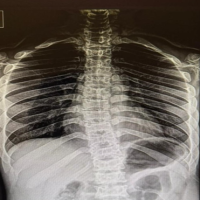

A 42-year-old right-handed male construction worker fell from a scaffold approximately 10 feet high. He landed with both arms outstretched and elbows extended. Upon presentation, the patient had gross deformity, pain, and swelling at both wrists and elbows. Upon inspection, deformities were seen on both wrists and elbows bilaterally. On examination, tenderness was found with a limited range of motion. Neurovascularity was intact in both upper limbs. X-rays revealed bilateral posterior elbow dislocation without associated fracture (Fig. 1a, b, c, d) and bilateral comminuted intra-articular distal radius fractures (AO 23-C2). (Fig. 2a, b, c, d). In the emergency setting, both elbow dislocations were promptly managed with closed reduction under sedation, and concentric reduction was confirmed on post-reduction radiographs (Fig. 3a, b, c, d). Both wrists were also reduced, and stabilization was done with slab application (Fig. 4a, b, c, d). Following initial stabilization and resolution of soft tissue swelling, the patient underwent staged open reduction and internal fixation of the bilateral distal radius fractures using a volar approach (modified Henry technique). Fixation was achieved using volar locking compression plates for both wrists (Fig. 5a, b, c, d).

Figure 1: X-rays showing posterior dislocation of the right elbow without any fracture in anteroposterior (a) and lateral (b) view and left elbow showing posterior dislocation of elbow without any fracture in anteroposterior (c) and lateral (d) view.